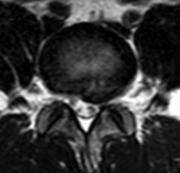

针对该患者的诉求,张昊主任与其团队进行了反复的讨论并分析小王的问题,首先,小王才15岁,但腰椎间盘突出明确并伴有椎体后缘离断,神经受压明显,导致下肢疼痛、麻木,严重影响日常生活和学习,经过一段时间保守治疗,仍反复,并且越来越明显了,因此针对青少年的腰椎间盘突出症患者治疗方面该如何定夺呢?张昊主任分析,结合该患者的特殊性,又要考虑患者以后的影响,把相关治疗方案以及相应的风险等事宜详细告知陈女士,最终在微创理念下采用脊柱内镜下腰椎间盘摘除技术为小王进行手术,手术切口1cm,术后症状缓解,恢复良好,效果非常满意,第二天顺利出院。

术后影像